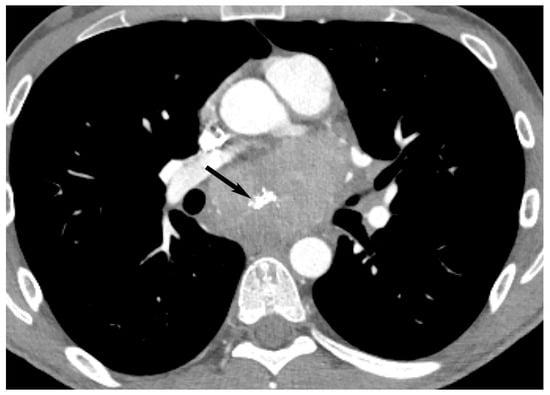

7. Germ Cell Tumors

9. Hypervascular Lesions